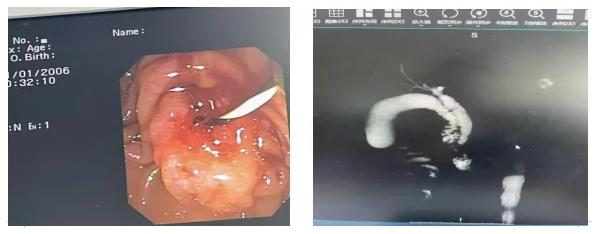

55岁的刘女士(化名)因反复上腹胀痛来到我院就诊。普外一科朱凡副主任医师接诊后,判断其病因很可能在于胆总管结石。在完善相关检查后,医疗团队为刘女士安排了“内镜逆行胰胆管造影术(ERCP)”的微创手术,旨在取出结石、解除梗阻。

在手术操作过程中,朱凡副主任医师发现了一个容易被忽略的细节:患者十二指肠乳头的形态异常,质地偏硬。“这不像普通的炎症或结石嵌顿。”凭借多年的临床经验,朱凡医生心中拉响了警报。他在顺利完成胆道扩张、放置引流管缓解患者症状的同时,果断地在异常部位进行了活检。

术后的病理报告证实了朱凡副主任医师的判断——十二指肠乳头腺癌。正是这次手术中细致入微的观察,让这个深藏的“定时炸弹”被提前发现。“这真是不幸中的万幸!”得知消息后,刘女士和家人既后怕又感激。由于发现得早,癌症仍处于可完全切除的早期阶段,刘女士的预后效果将大大提高。